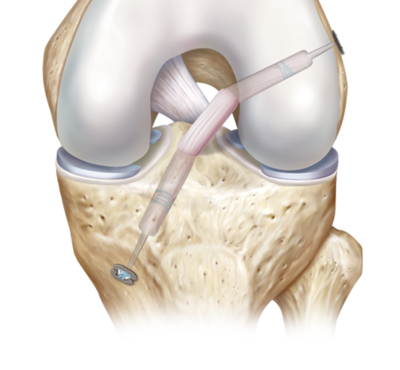

ACL Reconstruction

The most commonly injured ligament around the knee that requires surgical intervention is the anterior cruciate ligament (ACL). A typical mechanism of injury for tearing this structure is a non-cont..